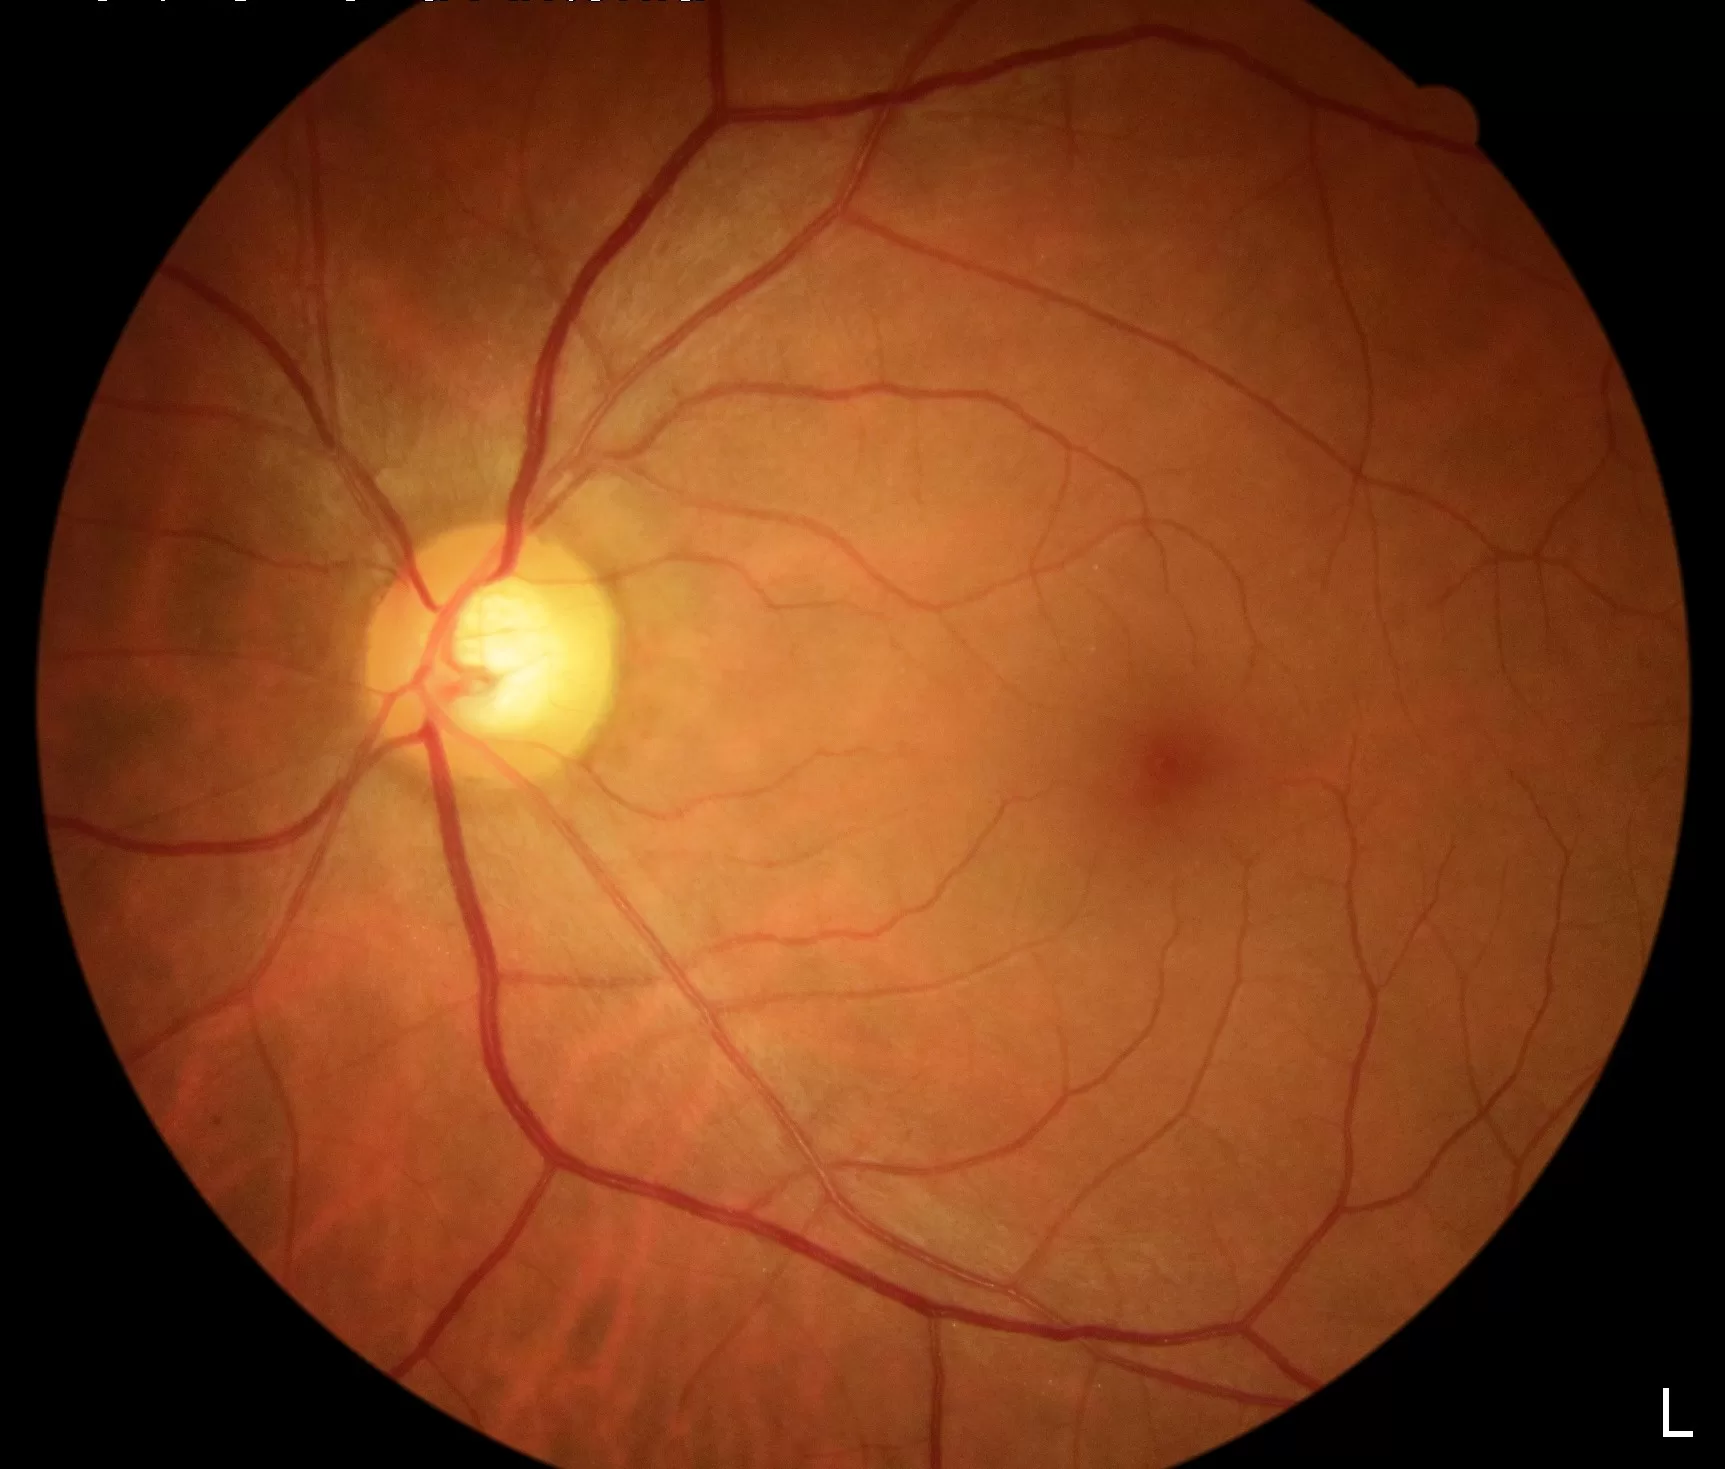

Doenças e Sintomas

Consciencialização sobre o glaucoma — o ladrão silencioso da visão.